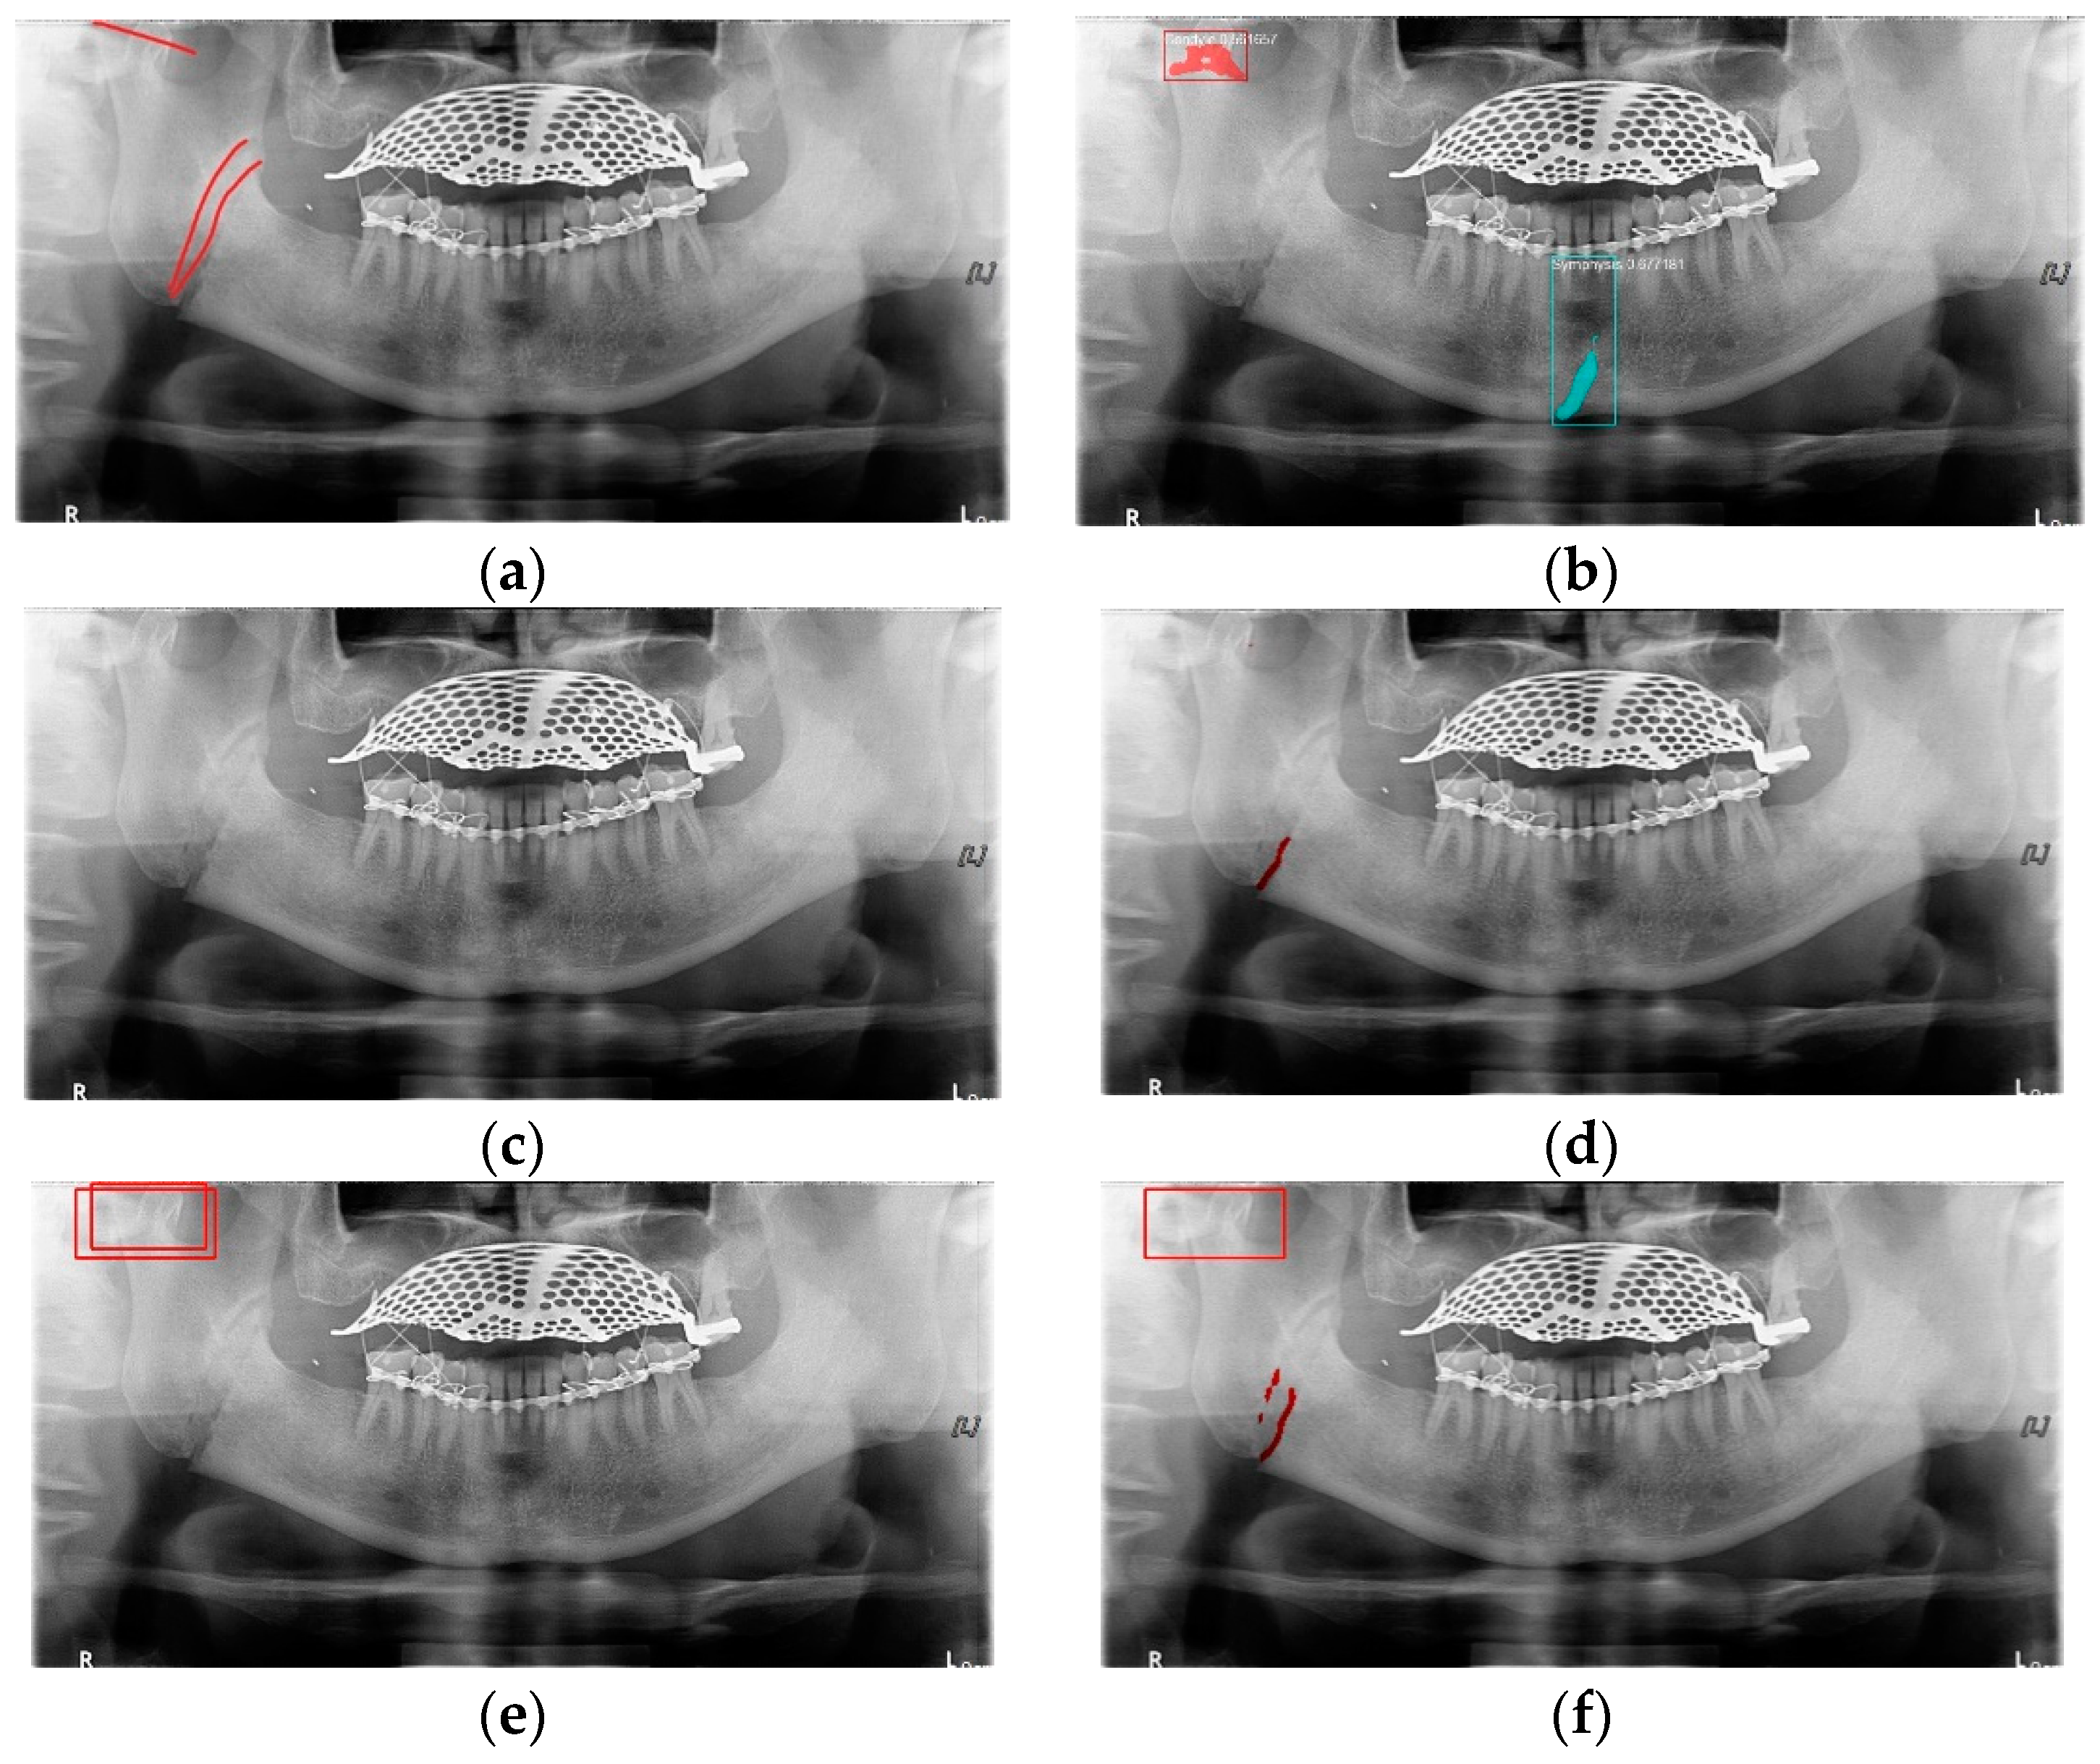

In Table 6, the parameters used for training are indicated, and in Figure 11, Figure 12 and Figure 13, the results of the doctor’s diagnosis, Mask R-CNN, YOLOv4, U-Net, LAT YOLOv4, and U-Net withYOLOv4 are compared. Figure 11 illustrates fractures in the angle and condylar regions, and in Mask R-CNN, the symphysis is misdiagnosed as a fracture. In Figure 12, the Mask R-CNN misdiagnoses the symphysis as a fracture, the result of the fact that the YOLOv4 module has better performance detecting angle fractures rather than does the LAT YOLOv4, as shown in Figure 12c,e. In short, the LAT-processed image does not always have the advantage of better revealing fractures compared with the normal panoramic radiograph.

Figure 11.

The comparison of mandibular fracture detection: (a) oral and maxillofacial radiologist, (b) Mask R-CNN (with colored polygons and boxes), (c) YOLOv4, (d) U-Net (with a red line), (e) LAT YOLOv4 (with red boxes), and (f) U-Net with LAT YOLOv4 (with a red box and lines).

Figure 12.

The comparison of mandibular fracture detection: (a) oral and maxillofacial radiologist, (b) Mask R-CNN (with colored polygons and boxes), (c) YOLOv4 (with a red box), (d) U-Net (with a red line), (e) LAT YOLOv4, and (f) U-Net with LAT YOLOv4 (with a red line).

Figure 13.

The comparison of mandibular fracture detection: (a) oral and maxillofacial radiologist, (b) Mask R-CNN (with colored polygons and boxes), (c) YOLOv4 (with a red box), (d) U-Net (with red lines), (e) LAT YOLOv4 (with red boxes), and (f) U-Net with LAT YOLOv4 (with a red box and lines).

In Figure 13, the ramus is misdiagnosed as a fracture. Therefore, Mask R-CNN had the lowest precision score because the misdiagnosis rate was higher than that of the other modules (Figure 16). The YOLO module has a low misdiagnosis rate, while the ‘undiagnosis’ rate is high; therefore, the F1 score is low owing to the ’undiagnosis’ rate. As shown in Figure 11, Figure 12 and Figure 13, YOLOv4 and LAT YOLOv4 have strong advantages over location information; therefore, they tend to detect well in the condyle region, that is, the side fracture, while they tend to detect poorly in the symphysis, body, and angle regions, where location information is ambiguous. Unlike Mask R-CNN and YOLO, U-Net is an image segmentation deep learning network, not an object detection deep learning network and labels mandibular fractures. U-Net marks fractures as lines on the label during training; however, it is difficult to label dislocated fractures, such as condyle fractures (Figure 11). Therefore, in the U-Net module, the side fracture was not diagnosed or misdiagnosed, and the precision-recall score was lower than that of the YOLO modules. It was judged that if the two deep learning networks are used together, the shortcomings of YOLO and U-Net complement each other and help improve mandibular fracture performance. In the proposed module, duplicate boxes that occurred in LAT YOLOv4 were removed before merging with the U-Net. In the proposed U-Net with LAT YOLOv4, the precision score was reduced; however, many ‘undiagnoses’ were eliminated; therefore, the recall score was increased, and it can be observed that the overall F1 score improved the performance by more than 90%.